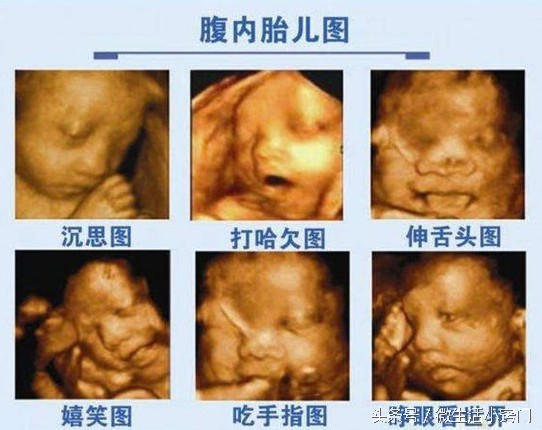

四维彩超:20-28周,四维彩色超声诊断仪是目前世界上最先进的彩色超声设备。其结果是:能够显示您未出生的宝宝的实时动态活动图像,或者其它人体内脏器官的实时活动图像。通过四维彩超可以知道胎儿性别,,我国禁止性别鉴定。目前仅私立医院可做。